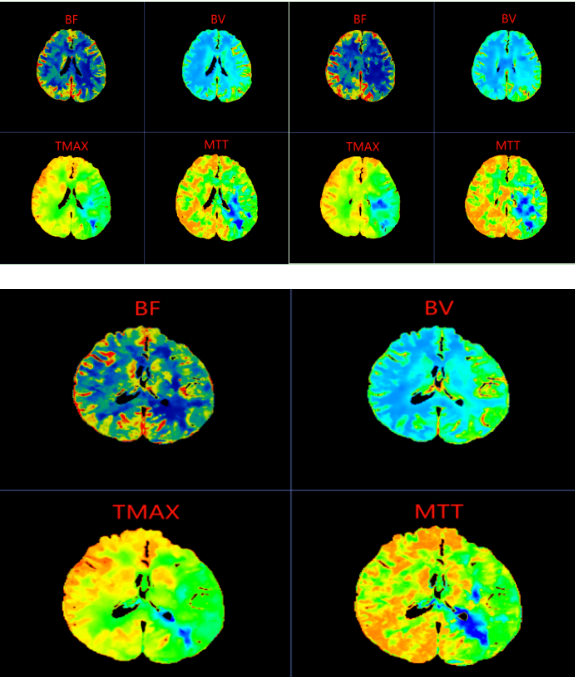

图像中,颜色映射左侧大脑半球显示局部脑血流量(CBF)下降,而脑血容量(CBV)可能基本正常或轻度升高,提示脑血管正在代偿性扩张以维持供血,但已濒临失代偿边缘。

左侧大脑中动脉供血区灌注异常:大脑中动脉是供应大脑半球外侧大部分区域的主要血管,一旦其血流减少,会影响语言、运动、感觉等重要功能。

I2期改变:属于“血流储备能力下降”阶段,意味着脑组织虽未完全梗死,但已处于“缺血半暗带”状态——这是可逆的关键窗口期。